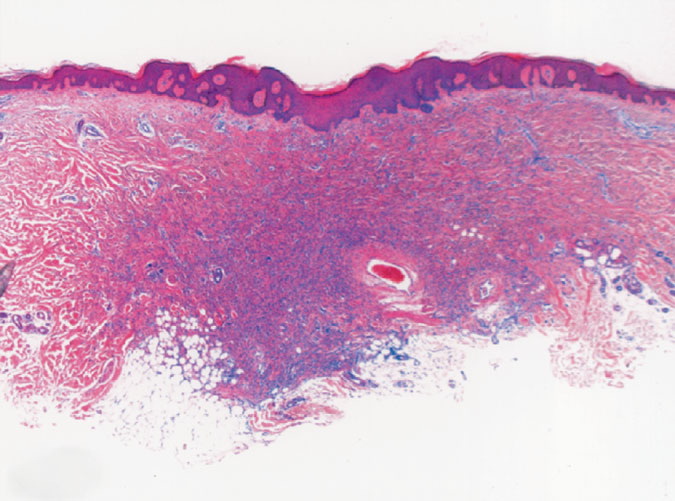

Skin Cancer and histopathology = سرطان الجلد